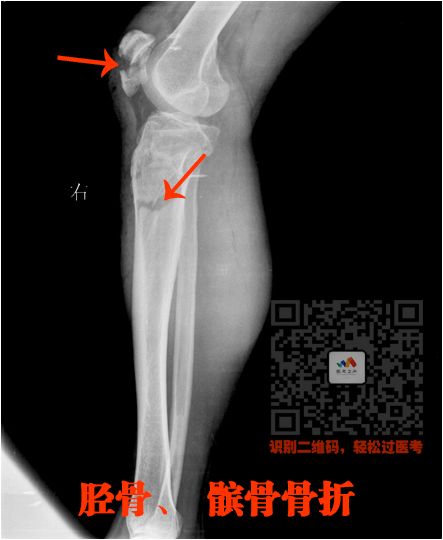

四、长骨骨折

就是四肢的长骨骨折

下肢:

股骨、股骨头、胫骨、腓骨

骨折非常简单的

这里就不讲解了,大家看片就行

看片